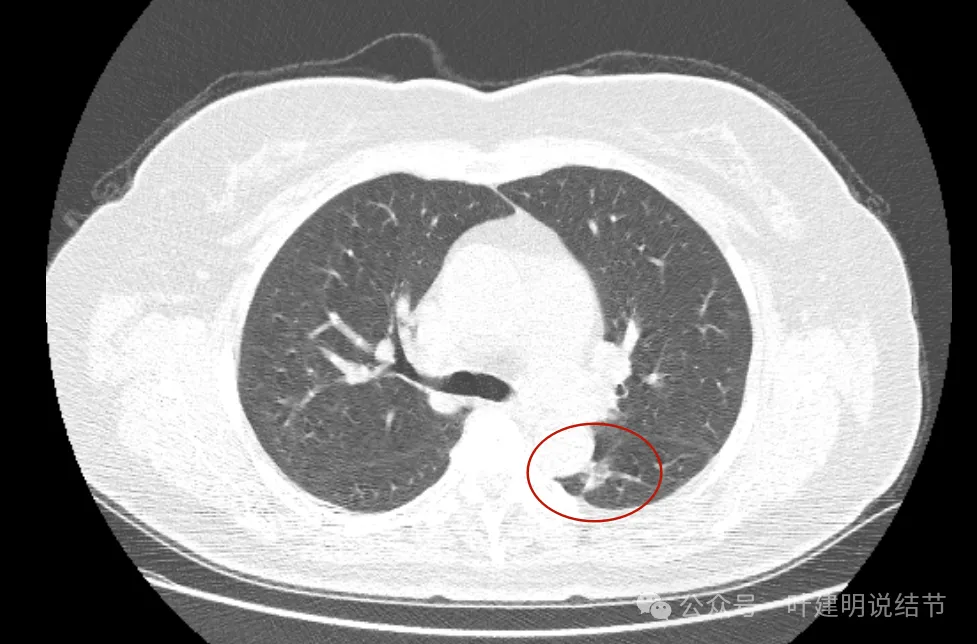

先看2019年时的影像:

病灶出现,密度不纯,有点状高密度成分,表面不光滑不平整。

实性成分为主,但边缘缺乏膨胀性,长刺较细长,感觉更像慢性炎。

上图密度较高,大部分实性,灶内略杂乱,与主动脉壁之间稍有缝隙,对应胸膜略有增厚,整体轮廓较清。

这样的病灶首次发现,虽不能完全除外恶性,但慢性炎的解释相对更符合些,肯定是要先随访观察或消炎后复查再对比。